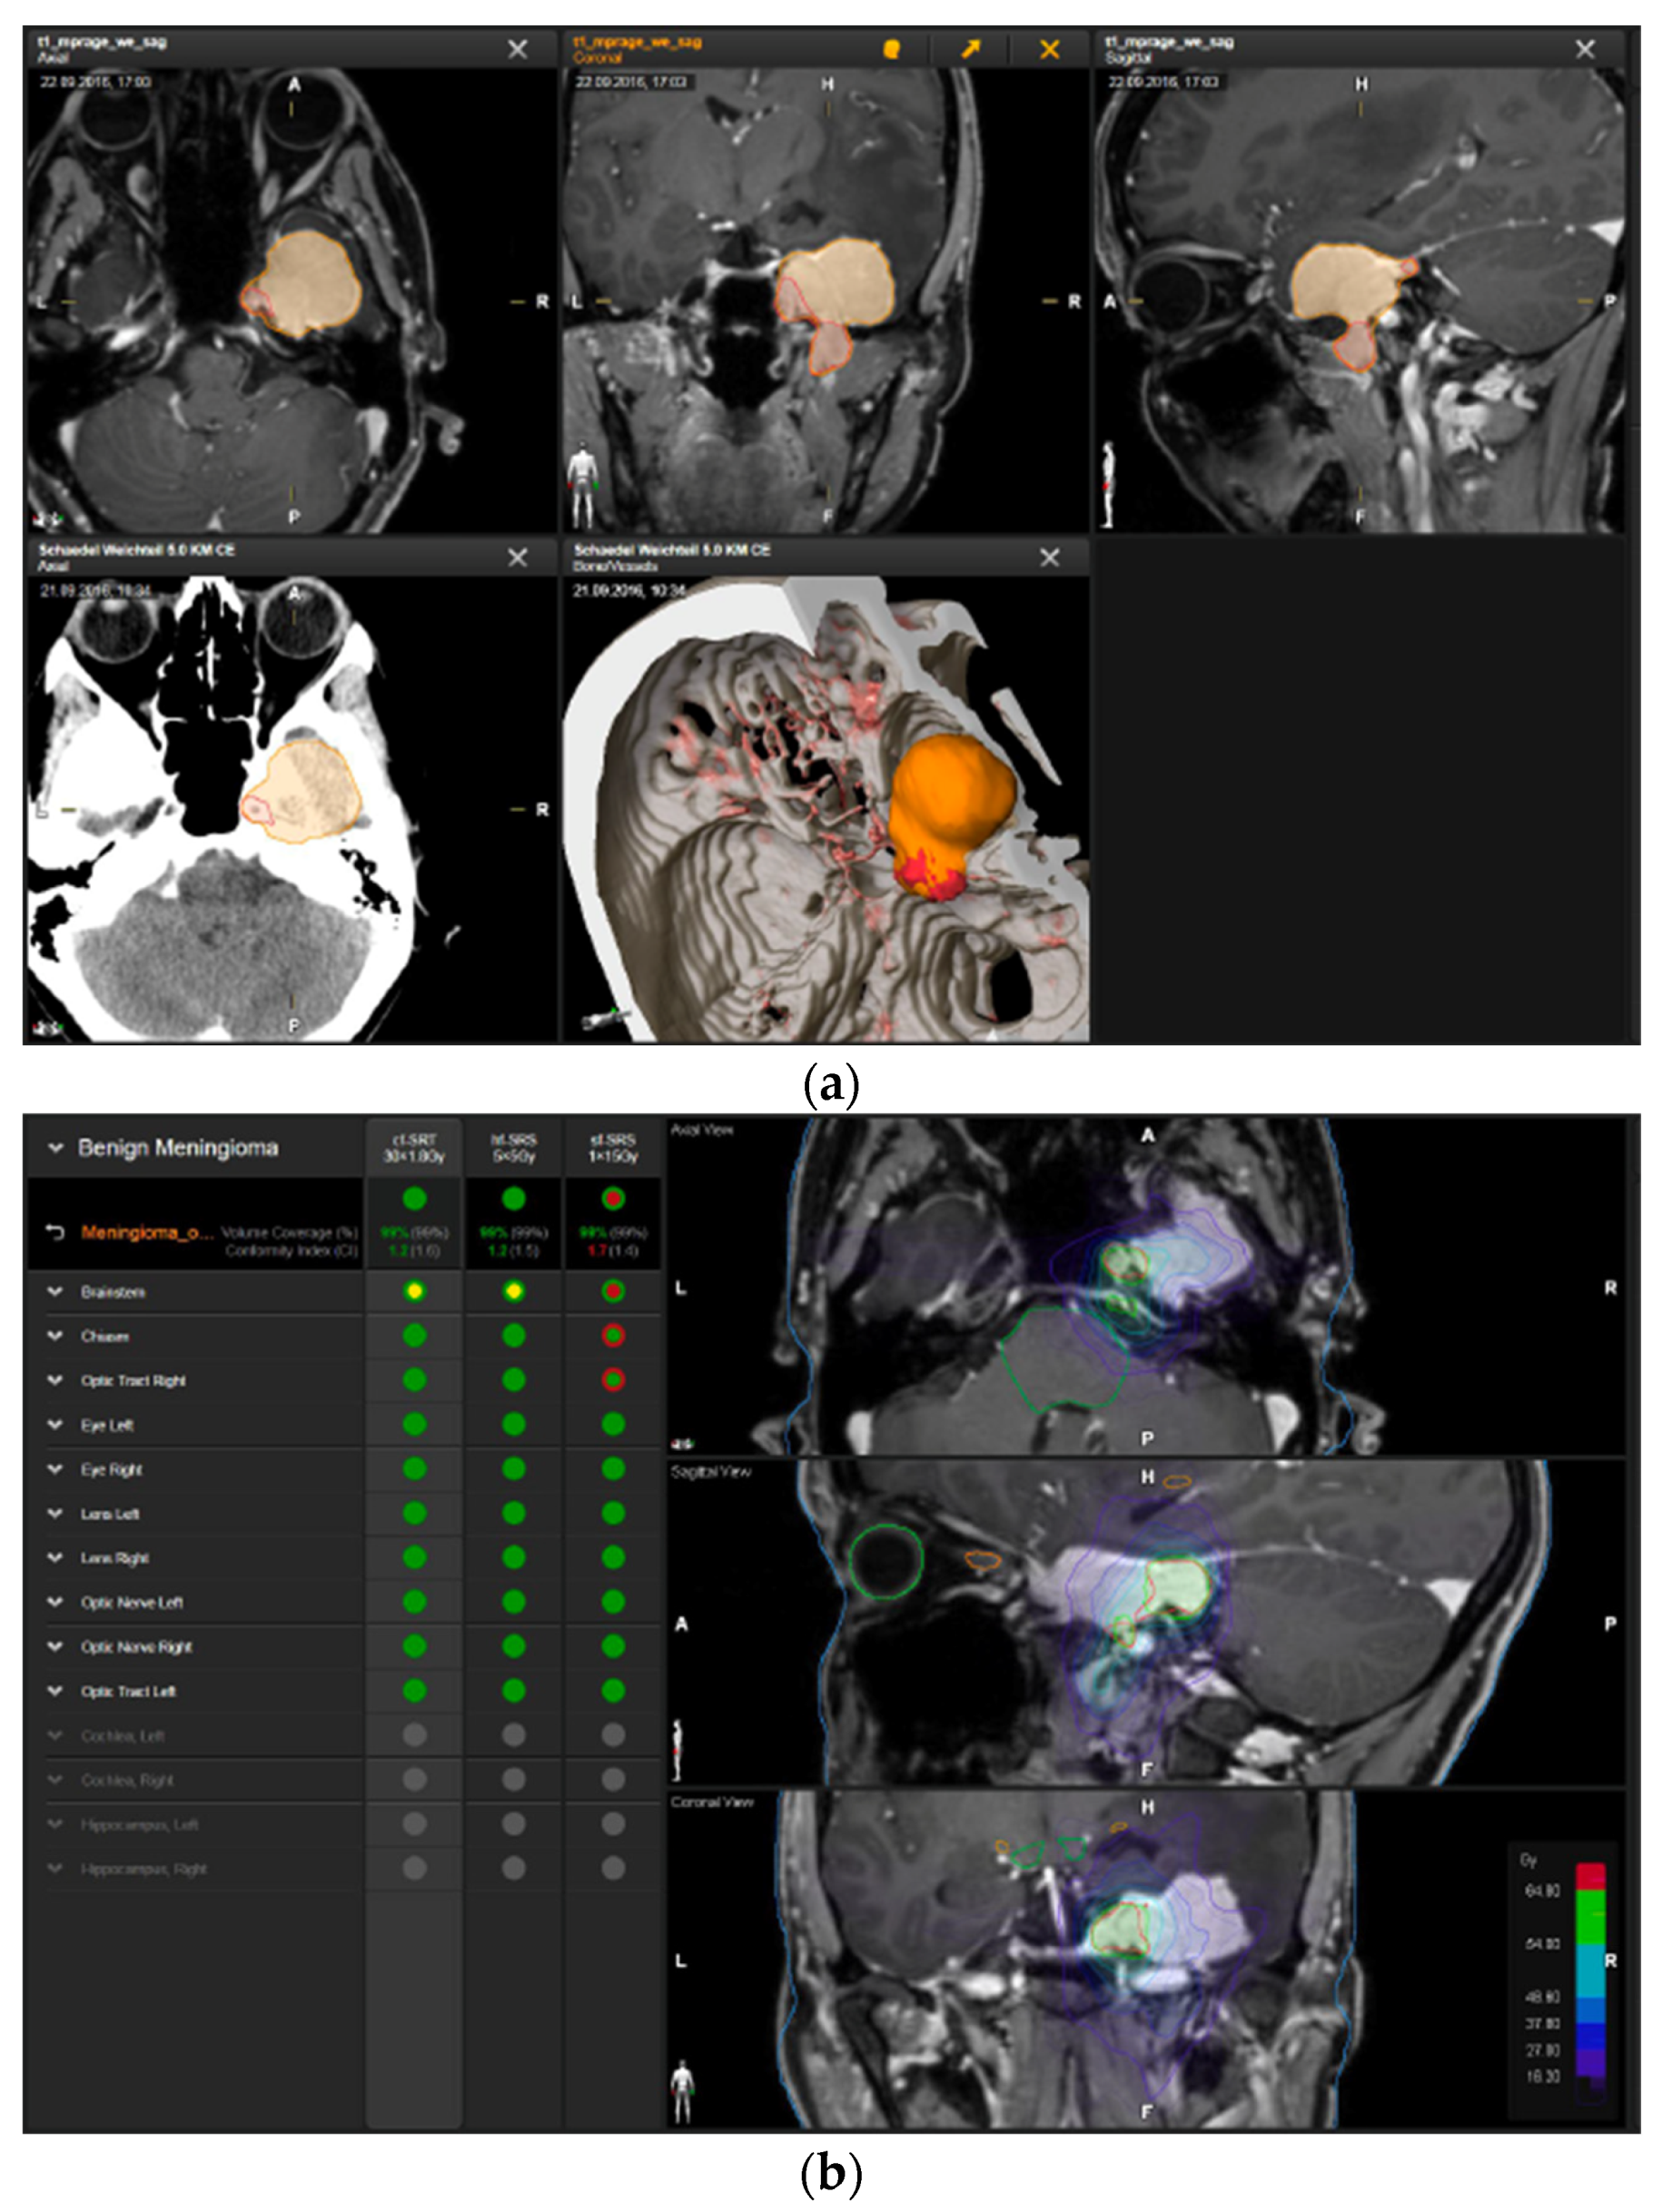

A 58-year-old female presented with progressive headache, difficulty swallowing, diplopia, hearing loss, and reduced face sensitivity on the right side (Figure 4). Elective craniotomy and AHSA-assisted tumor resection were performed. The patient underwent hypofractionated radiosurgery (5 × 5 Gy) of the residual meningioma one year after tumor resection.

Figure 4.

Second representative case of AHSA-supported tumor resection. (a) MRI imaging of petroclival meningioma (axial, coronal, sagittal). (b) Depiction of preoperative tumor volume (orange) and planned residual tumor volume (red). (c) AHSA summary table showing the stereotactic radiation constraints for the preoperatively planned residual tumor volume. With this plan, conventional fractionation and hypofractionation were feasible with effective tumor coverage.

—brainstem: mean dose is safe, while the max. dose is marginally safe;

—right optic tract: mean dose unsafe, max. dose is marginally safe;

—right hippocampus: marginally safe, and mean dose unsafe, max. dose is marginally safe. (d) First intraoperative structure update (ISU) with a residual tumor volume of 82% with the calculated dose constraints for conventional and hypofractionated radiotherapy. Single dose stereotactic radiosurgery was not feasible with this degree of remaining tumor. At this point, the dose constraints for conventional radiotherapy were:

—brainstem: mean dose is safe, max. dose is marginally safe;

—right hippocampus: mean dose unsafe, max. dose is marginally safe. Hypofractionated radiotherapy:

—brainstem: marginally safe;

—right cochlea: mean dose unsafe, max. dose safe;

—right hippocampus: mean dose unsafe, max. dose is marginally safe. (e) Second intraoperative ISU with residual tumor volume of 74% and calculated dose constraints for hypofractionated radiotherapy. Single dose stereotactic radiosurgery was still not considered feasible with this residual tumor volume. The dose constraints for organs at risk for conventional and hypofractionated radiotherapy were unchanged compared to the first ISU. (f) Third intraoperative ISU with residual tumor volume of 47% and calculated dose constraints for conventional, hypofractionated radiotherapy, and radiosurgery. The current dose constraints for organs at risk were the following for conventional radiation:

—right hippocampus: mean dose unsafe, max. dose is marginally safe. Hypofractionated radiation, which was unchanged for the first and second ISU:

—right hippocampus: mean dose unsafe, max. dose is marginally safe. For single fraction radiosurgery, the OAR dose constraints were available but considered to be unsafe.

—brainstem: mean dose unsafe, max. dose safe;

—chiasma: unsafe;

—right cochlea: unsafe;

—left optic tract: mean dose unsafe, max. dose safe;

—right optic tract: unsafe;

—right hippocampus: unsafe. (g) Overlay of preoperatively estimated and intraoperative effective residual tumor volume in AHSA. (h) Final intraoperative dose constraints after last ISU and data fusion with intraoperative CT. The dose constraints for OARs appeared to improve and were as follows for conventional and hypofractionated radiotherapy:

—brainstem: mean dose is safe, max. dose is marginally safe.

—brainstem: mean dose safe, max. dose unsafe;

—chiasm: mean dose unsafe, max. dose safe;

—right optic tract: mean dose unsafe, max. dose safe. (i) Comparison of pre- and 3 months postoperative MRI for stereotactic radiation planning. The residual tumor was finally treated with hypofractionated radiotherapy (5 × 5 Gy).